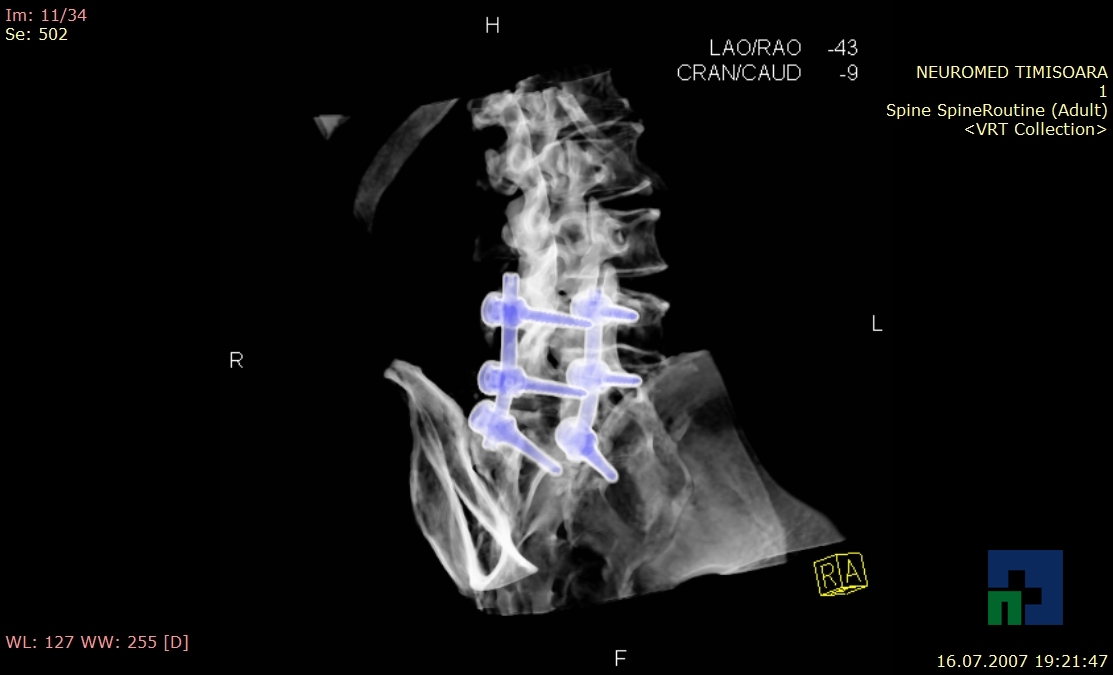

Examinare de rutină cerebrală, nativ și cu substanță de contrast (SDC) pentru diagnosticul:

- Diagnosticul fracturilor:

- Unice

- Multiple

- Cu înfundare